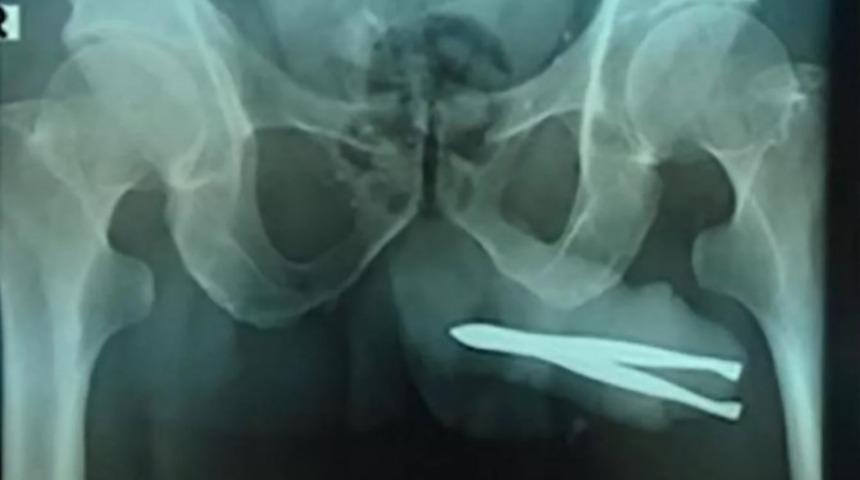

MYNET|DIŞ HABERLER Endonezya'da yaşanan bir tıbbi olay kısa sürede ilgi çekmeyi başardı. 54 yaşındaki ismi açıklanmayan bir hasta çığlık çığlığa hastaneye geldiğinde doktorlar röntgen çekerek nedenini öğrenmek istedi.

İsmi açıklanmayan 54 yaşındaki adam, acıya rağmen mucizevi bir şekilde idrarını yapmayı başardı. Hasta her tuvalete gittiğinde acı içinde çığlık atıyordu. Onu tedavi etmek için, anestezi altında cımbızın cinsel organından çıkartılması gerekiyordu. Cerrahi operasyonla nesne çıkartırıldı.